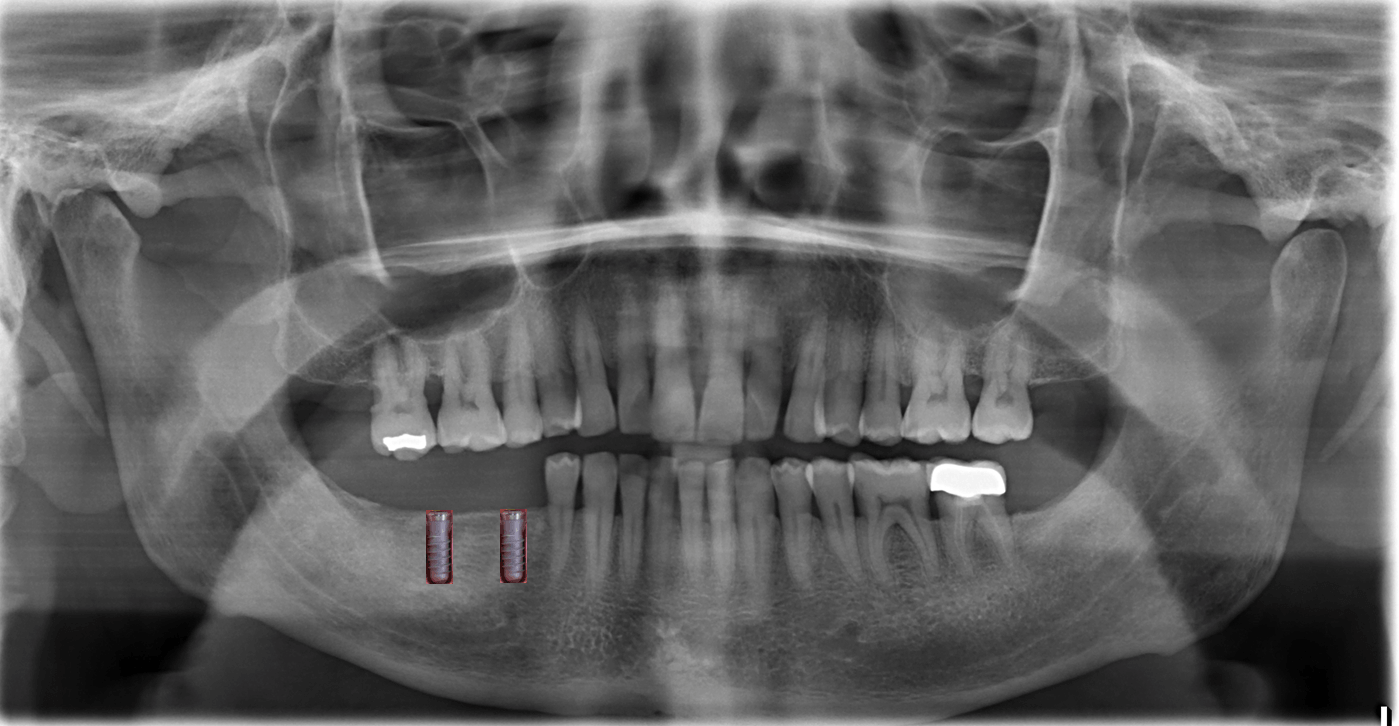

X-ray, 3D and examination

The basis of the final plan

A 3D examination "digital volume tomography" is carried out in the DVT Center Hamburg, Lerchenfeld 14, 22081 Hamburg, Tel 040-2269-4990. They will give you the CD, which we will read here.